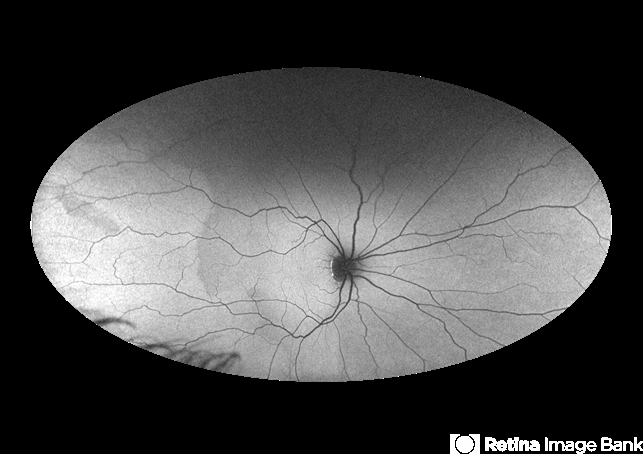

- Foveal hypoplasia

- foveal hypoplasia, nystagmus, autofluorescence imaging, ultra-wide field imaging

- This is a wide field autofluorescence image of 21 year-old male. He presented with history of low vision since childhood associated with nystagmus. Uniform fluorescence across posterior pole with absent foveal hypo autofluorescence can be seen on the image.